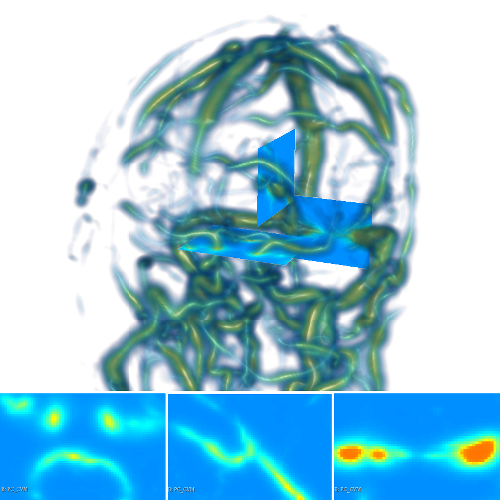

3.2 Connected Geodesic Paths as Vascular Tree

Representative examples of degraded synthetic images from SVT and the respective GT are shown in fig. 4 together with the connected graphs extracted by VTrails. Analogously, the same set of images are reported for the real images TOF and CTA in fig. 4. Qualitatively, the extracted set of connected geodesic paths shows remarkable matching with the provided GT in all cases. First, we verify the acyclic nature of the graph. We found no cycles, degenerate graphs and unconnected nodes, meaning that the extracted connected geodesic paths represent a connected geodesic tree. Precision and recall are then evaluated for the identified branches. Also, error distances are determined as the connected tree’s binary distance map evaluated at GT. Average errors () precision and recall are reported (meanSD) in table 1. Note that no pruning of any spurious branches is performed in the analysis.

| Synthetic Vascular Trees (SVT) [10] | Clinical Angiographies | ||||||

| Image | GT | VTrails | Image | GT | VTrails | ||

| N1 |  |

|

|

CTA |  |

|

|

| N2 |  |

|

|

TOF |  |

|

|